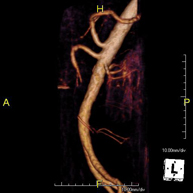

Prova diagnòstica no invasiva que consisteix en l'obtenció d'imatges d'alta definició anatòmica de tot el cos mitjançant l'ús d'un camp electromagnètic i ones de ràdio (amb un emissor i un receptor). No utilitza radiació ionitzant. És una prova molt important en la recerca de metàstasi en pacients amb neoplàsia coneguda. No requereix preparació prèvia. No és necessari l'ús de contrast paramagnètic (Gadolini). - Angio RM d'Aorta-ilíaca

Prova diagnòstica no invasiva que consisteix en l'estudi de l'artèria aorta abdominal per obtenir imatges d'alta definició anatòmica mitjançant l'ús d'un camp electromagnètic i ones de ràdio (amb un emissor i un receptor). És indispensable l'ús de contrast intravenós paramagnètic (Gadolini). No obstant, no utilitza radiació ionitzant. La qualitat de les imatges permet realitzar reconstruccions en 2D i 3D. Està indicat en aquells pacients amb malaltia vascular (Aterosclerosi), per a l'estudi d'aneurismes, en estudis prequirúrgics de lesions adjacents a l'aorta abdominal com "mapa" vascular, etc. - Angio-RM Aorta ilíaca

Prova diagnòstica no invasiva que consisteix en l'estudi de l'artèria aorta abdominal per obtenir imatges d'alta definició anatòmica mitjançant l'ús d'un camp electromagnètic i ones de ràdio (amb un emissor i un receptor). És indispensable l'ús de contrast intravenós paramagnètic (Gadolini). No obstant, no utilitza radiació ionitzant. La qualitat de les imatges permet realitzar reconstruccions en 2D i 3D. Aquesta prova està especialment indicada com estudi prequirúrgic (mapa vascular) abans d'intervencions percutànies o quirúrgiques d'aorta abdominal, per a l'estudi complementari en pacients amb isquèmia de membres inferiors, etc. - Angio-RM d'Artèries renals